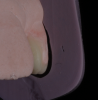

At the second appointment, the selected dentin and enamel shades were verified by placing small amounts of composite that were about 0.5-mm thick on the cervical area of the central incisor (Figure 19). After shade selection, isolation was achieved by placing a rubber dam from first bicuspid to first bicuspid (Figure 20), and the maxillary lateral incisors were disinfected with a 2.0% chlorhexidine gluconate solution and polished with contouring and polishing discs (Figure 21). Next, the surfaces were etched for 15 seconds with a 35% phosphoric acid etchant (Figure 22), and an adhesive agent was placed, softly air-dried, and light-cured for 60 seconds (Figure 23).

(19.) Pretreatment retracted close-up view of the maxillary arch with dots of composite placed on the maxillary right central incisor to verify the selected dentin and enamel shades.

Figure 19